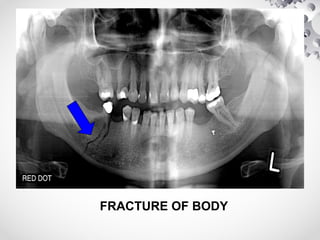

FRACTURE OF BODY

CLINICAL FEATURES

• # of Angle, Body & Symphysis

(1) Pain & paradoxical movement; crepitus on distraction of #

segments

(2) Blood stained saliva

(3) Anaesthesia of lower lip

(4) Step deformity palpable externally or intraorally

(5) Asymmetry of lower dental arch & malocclusion

(6) Hematoma in floor of mouth / buccal sulcus